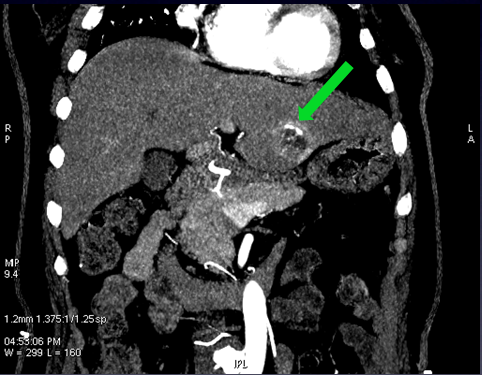

动脉期肝左叶病变,亦呈早期边缘强化

轴位图像观察到的左右叶病变